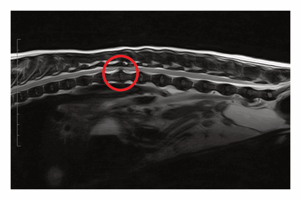

Imagine this clinical scenario: a client brings in their pet dog that is presenting with acute abdominal signs. After talking to the owner, you suspect an intestinal obstruction which, if diagnosed, could require surgical intervention. You recommend carrying out some diagnostic imaging tests to identify any intestinal obstructions, including an abdominal radiograph and ultrasonography.

Due to the client’s financial constraints, you can only use one diagnostic imaging method. You decide to consult the evidence to find out whether radiography or ultrasonography is superior at detecting the need for surgical intervention by accurately diagnosing small intestinal mechanical obstruction.

Drost et al. (2016) and Elser et al. (2020) studied the diagnostic accuracy of radiography. The first paper examined 20 dogs that were diagnosed with mechanical intestinal obstruction and evaluated with radiography. The outcomes studied that are relevant to the research question were signs of gastrointestinal obstruction and diagnosis of mechanical obstruction. In comparison, Elser et al. studied 40 dogs with suspected gastrointestinal obstruction. The outcomes studied were sensitivity, specificity and percentage accuracy of the radiography.